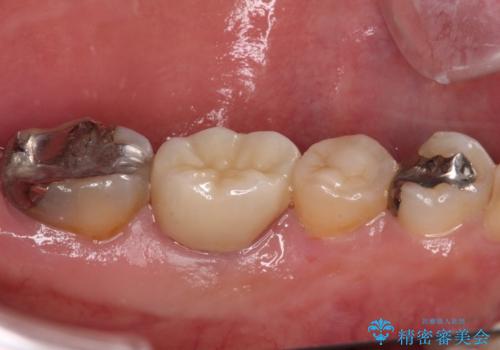

- 根っこの一部だけになった歯と咬むと痛みのある歯を気にして来院された患者様です。

上顎の歯根のみとなった歯は抜歯が必要であったので、抜歯を行い、インプラントあるいはブリッジのよる補綴治療を提案しました。

前後の歯は銀歯が装着されていたため、ブリッジによる補綴治療として、前後の歯もセラミックに置き換えることとしました。

下顎の根管治療がされた大臼歯は咬合時に痛みが認められたため、再度根管治療を行った後に補綴治療することとしました。